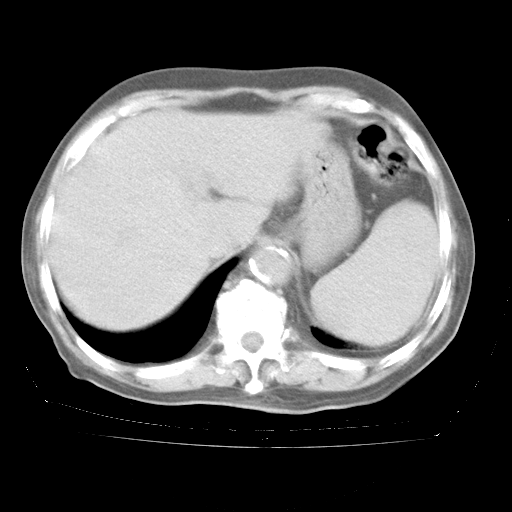

4月28日肺部CT——再次出现类似去年5月9日——透光度降低,“间质性”改变。

4月28日肺部CT——再次出现类似去年5月9日——磨玻璃样、间有“粟粒样”改变。

4月28日肺部CT